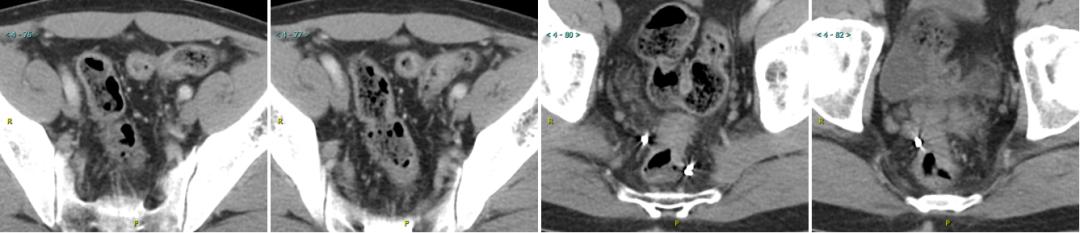

2017.11超声和CT

腹部超声:肝内多发性占位病变性质待查,结合病史考虑转移性肝癌可能,其它疾患待排,建议超声造影。

胸腹部增强CT:1.“右半结肠癌术后”,吻合口远侧复发肠癌,CT分期 rT3N0M1a;2.肝S3、S6病变,结合病史,考虑转移。

▲上:2016.12.21;下:2017.11.14。